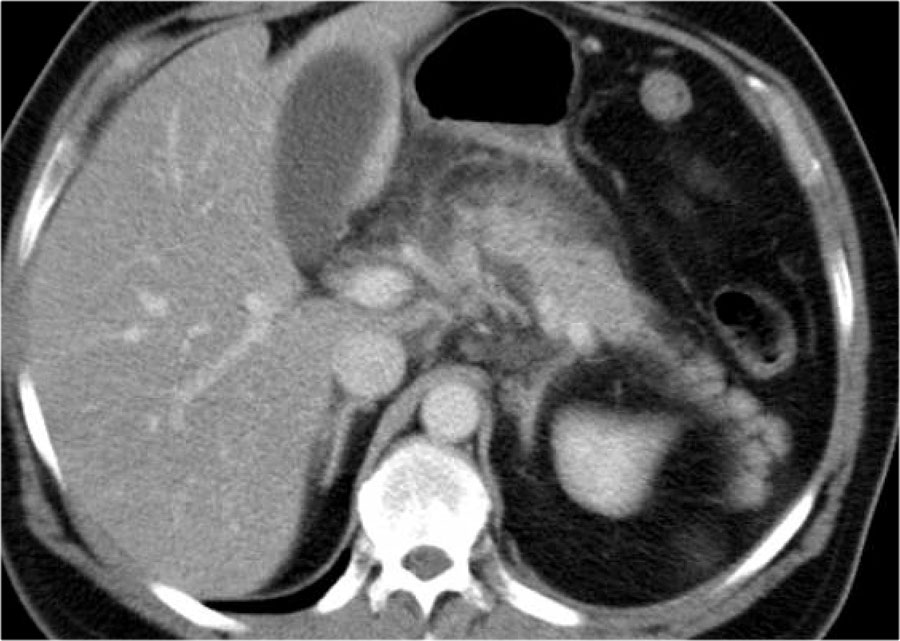

Các hình ảnh cho thấy tụy ngấm thuốc bình thường vào ngày thứ 1.

Khi tình trạng bệnh nhân xấu đi, CT lần hai được thực hiện vào ngày thứ 3.

Lưu ý phần lớn thân và đuôi tụy không còn ngấm thuốc, gợi ý viêm tụy hoại tử (các mũi tên).

CT lần đầu đã đánh giá thấp mức độ nặng của viêm tụy.

Bệnh nhân này tử vong vào ngày thứ 5 do hội chứng đáp ứng viêm hệ thống (SIRS) nặng và suy đa tạng.